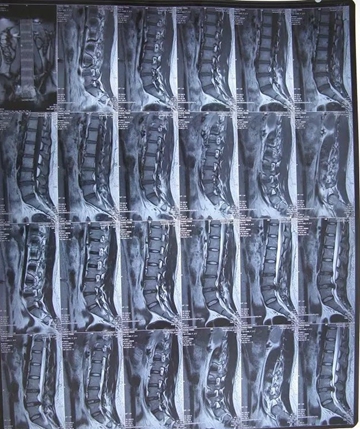

核磁矢状位

核磁轴位

2011年,小张(20岁),L4-5椎间盘脱出,高密人民医院、青岛山大医院要求手术。右腿外侧疼痛,迈不开步子,直腿抬高不过20°。